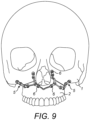

- the user may subsequently draw the implant 5 which can be seen in Figure 9 .

- the sixteen osteosynthesis screws which ensure that the implant is fixed in the first and second portions of the bone are designated by the locations 6. These screws correspond precisely to the fixing locations or attachment points 4, which can be seen in Figure 4 .

- the implant 5 is thus arranged at a pre-operative stage so as to correspond to the planned post-operative shape of the desired anatomy.

- the implant 5 is also pre-shaped in such a manner that the congruence of surfaces of intrados thereof allows unique and precise positioning on the two portions of bone to be joined at the end of the surgical operation.

- the implant 5 extends at both sides of one or more osteotomy lines 7.

- the one or more osteotomy lines 7 each define a cut containing the line which separates the two portions of bone 1, 2.

- the implant 5 may be manufactured or produced based on the defined structure, e.g. based on a three-dimensional model such as that shown in Figure 9 .

- Figure 9 shows a simulation of the two portions of the bone joined after an osteotomy and repositioning operations.

- Figure 9 is thus illustrative of the use of an implant 5 following surgical operations.

- the joining of the two portions of bone is securely held using the implant 5.

- the implant may remain indefinitely or as long as a medical professional deems it necessary to allow the two portions of bone to be fixed and consolidated. For example, in a case similar to Figure 9 bone may grow to join both the first and second portions in the configuration set by the implant 5.